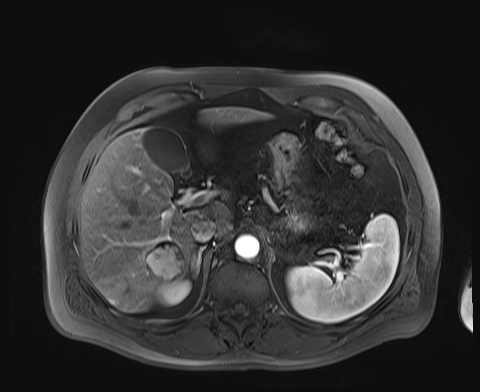

Case 3

20 F with PMH hypoplastic left heart s/p fenestrated Fontan procedure admitted for shortness of breath and hypoxia of uncear etiology.

145/58 mmHg / 78 bpm / 20 breaths/min / 97.6°F / 88% 6L

Faint expiratory wheezing in upper lungs, rhinorrhea, and congestion

AST 33, ALT 33, Alk Phos 222